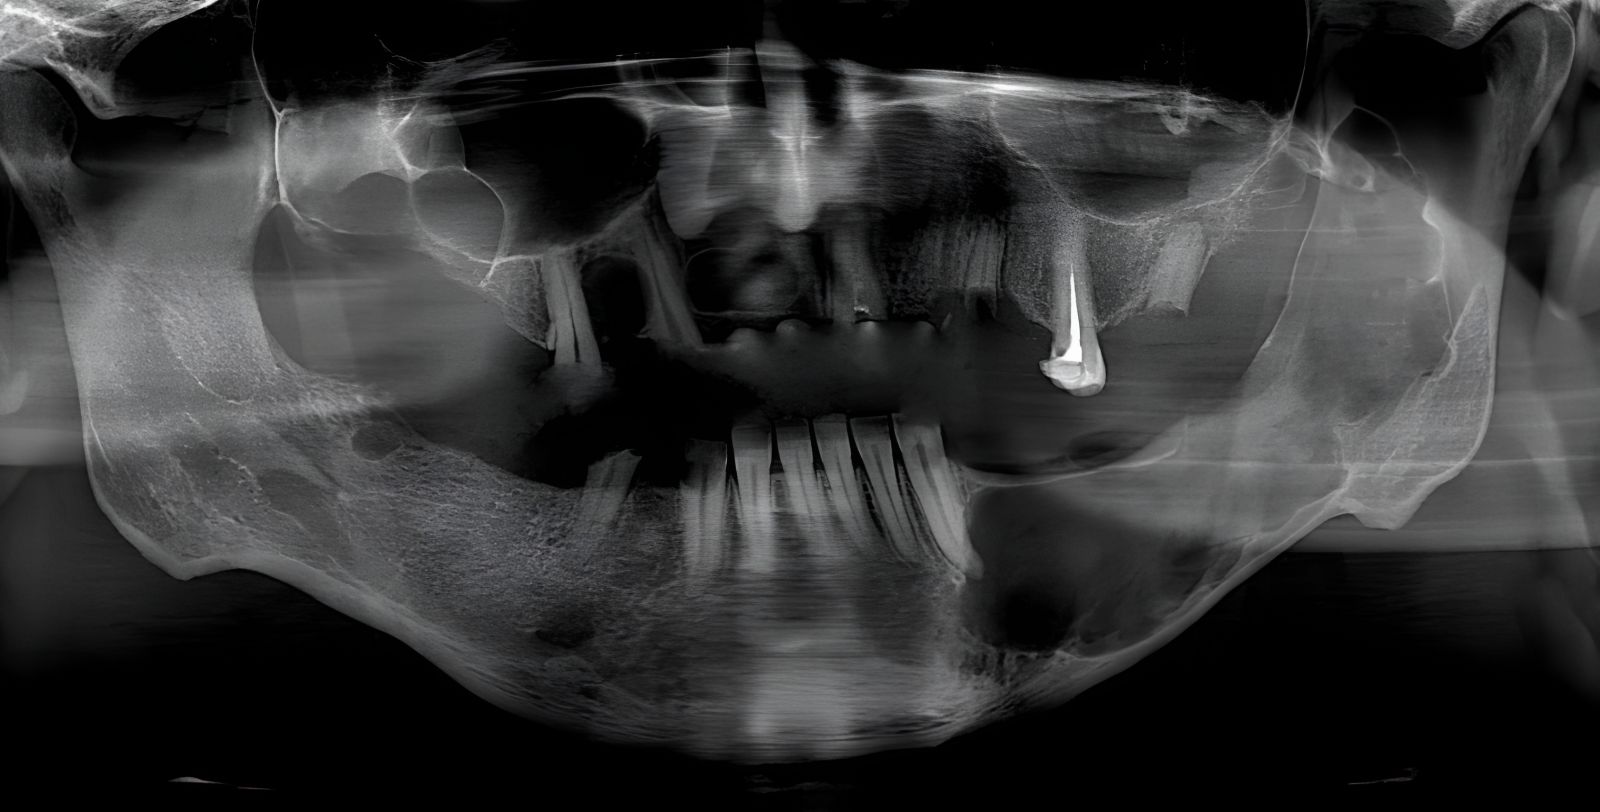

يصارع الناشط الفلسطيني السوري "أيمن دواه"، من أبناء مخيّم اليرموك المهجر إلى منطقة أسنيورت بمدينة إسطنبول مرضاً خطيراً: سرطان الأنمو بلاسما في الفكين - ورم خبيث ينهش عظامه ويحول وجهه إلى ساحة معركة يومية مليئة بالألم الشديد والتنفس الصعب.